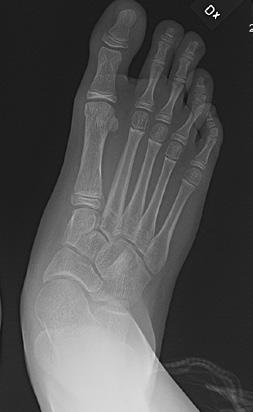

Den typiska stortåfelställningen (se bild 1) orsakas av en muskelobalans, som måste korrigeras tillsammans med stortåkirurgin för att resultatet ska bli bestående.

Sannolikt normalt/fysiologiskt hos barn om den är bilateral. Plattfothet undersöks bäst bakifrån när barnet står på hela foten och sedan ställer sig på tå. Då ser man hur bakfoten går från valgus vid belastning till varus vid tåstående. Likaså kan man se att det utvecklas ett längsgående medialt fot valv när barnet ställer sig på tå jämfört med när hela foten belastas. Se bild 1.

Sannolikt. Plattfotheten beror nog mest på flexibla fötter som inte har något strukturellt fel. Observera att det normala är bilateral plattfothet. Unilat eral betyder att en fot är platt, pes plano valgus, eller att den andra är i varus, ibland cavo varus, vilket inte är normalt. Om det finns en tydlig asym metri och fotfelställningen är förvärvad behöver man tänka på möjlig neuropati eller pro cess i spinalkanalen. Se bild 2.